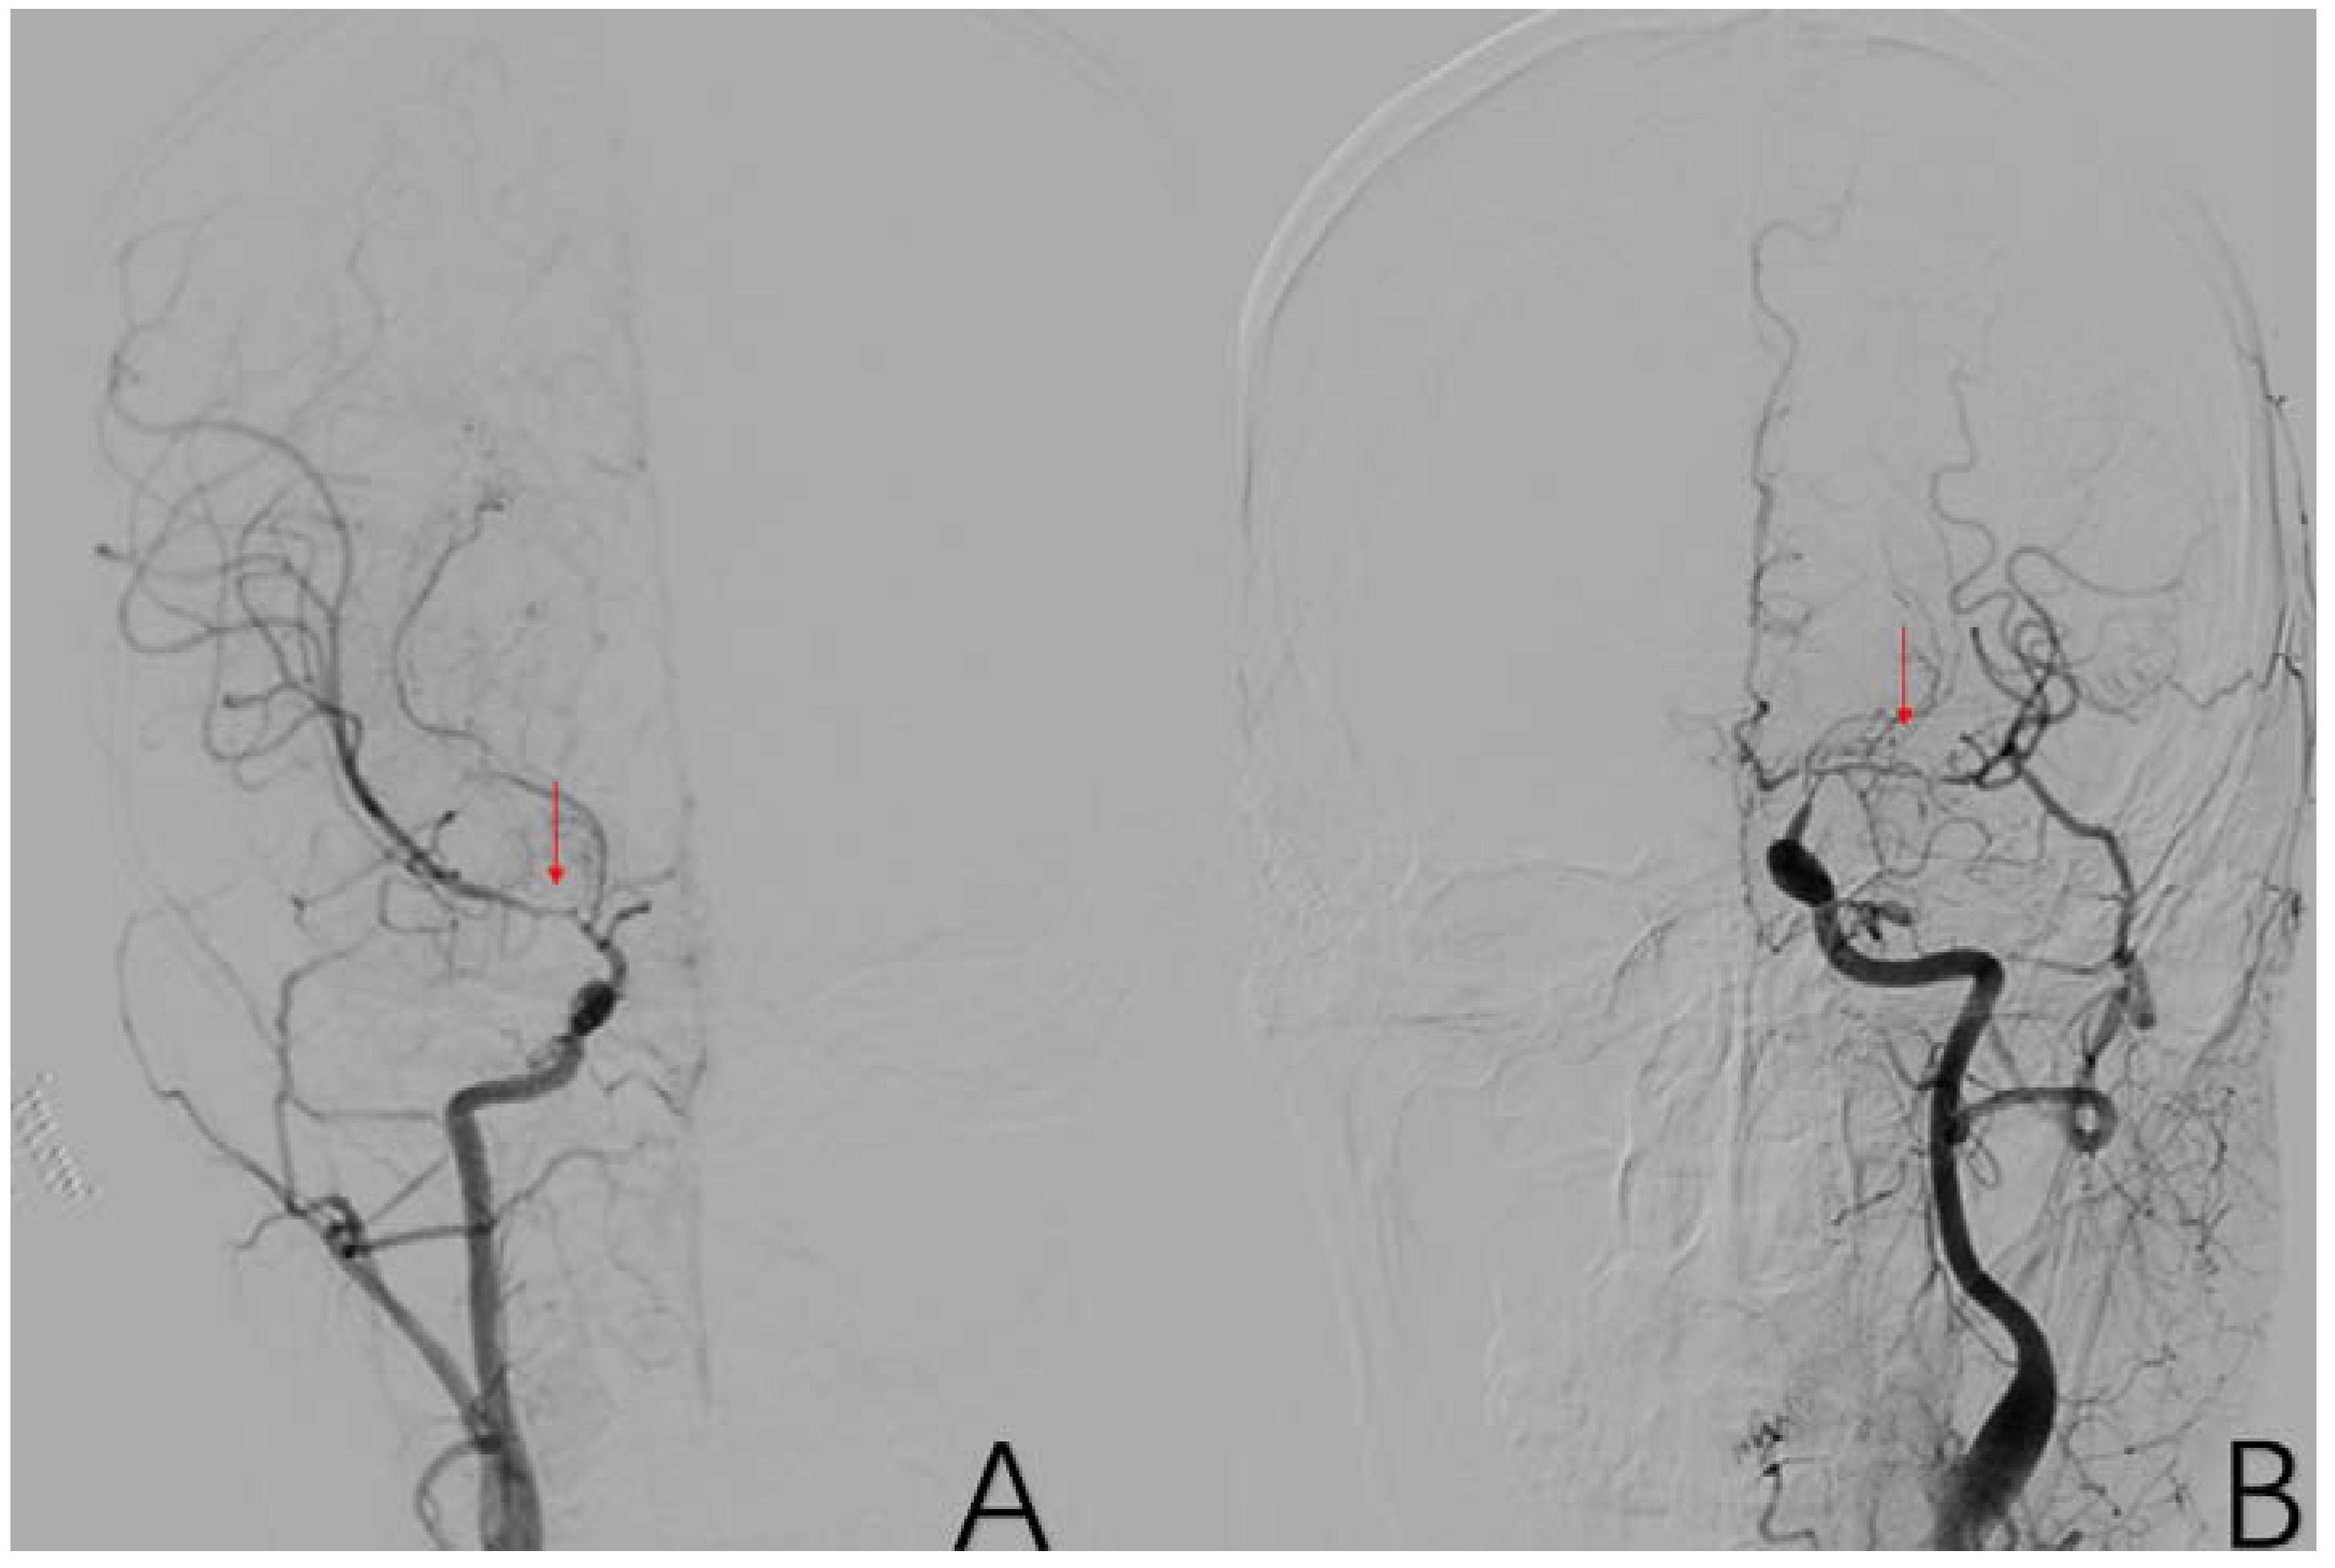

2.3.12. Factor 7 Extracranial Arterial Compensation

2.3.10. Factor 5 Posterior Circulation Compensation

2.3.11. Factor 6 Unstable Compensation